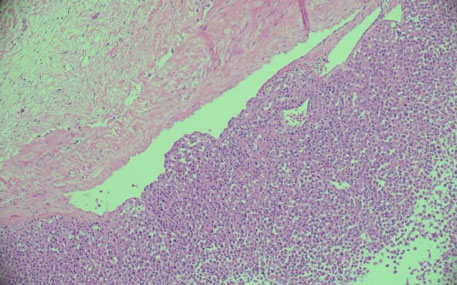

The histological characteristic of OAC is the presence of large polygonal cells with abundant eosinophilic cytoplasm, as a result of mitochondrial accumulation [3]. The diagnostic criteria used for ACC, the Weiss system, overestimates malignant potential in oncocytic tumors, therefore a separate classification system called the Lin–Weiss–Bisceglia (LWB) classification is used for oncocytic tumors [5],[8]. The LWB system divides oncocytic adrenocortical neoplasms (OANs) into benign, borderline, and malignant categories based on three main criteria: a mitotic rate greater than 5 per 50 high-power fields, vascular invasion, and metastasis. Malignancy is diagnosed if any of these criteria are present, while borderline tumors show only minor criteria, such as a tumor size greater than 10 cm, necrosis, or capsular invasion. This classification system has enhanced the ability to differentiate between benign oncocytic adenomas and OACs. In our patient, the resected specimen showed a well-circumscribed tumor weighing 5458 g, and measuring 26.0 × 25.0 × 16.0 cm. The tumor also had extensive hemorrhage and necrosis, along with a central fibrous scar [9]. Microscopically the patient’s tumor matched the classic histological findings for OAC and exhibited a low Ki-67 index of 2% suggesting a low proliferative rate. However, the tumor did exhibit vascular (renal vein) and capsular invasion (Figure 3, Figure 4, Figure 5, Figure 6). Based on the LWB criteria, malignancy was established due to the vascular invasion. Next-generation-sequencing (NGS) showed TP53 pathway alterations. The malignancy had a low tumor mutation burden and was found to be microsatellite stable. These findings are consistent with recent research suggesting a distinct mitochondrial metabolic profile with an oncocytic variant of ACC [4].

Figure 6: Tumor with vascular invasion.

Share Image: